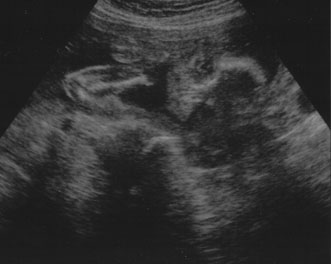

A second trimester ultrasound is usually done at 20 to 22 weeks' gestational age. The most commonly used fetal measurements are biparietal diameter, length of the femur or other long bones, and abdominal and head circumference. In addition to measurements, an anatomic survey is also done to evaluate the fetal brain (Fig. 9), spine, stomach, heart, kidneys, placental location and assessment of amniotic fluid (Fig. 10). If maternal risk factors are present, tetra screening results are abnormal, or there are abnormal findings on the anatomic survey, the patient is sent for a comprehensive ultrasound. The components of a comprehensive ultrasound are shown in Table 9. The ultrasound findings associated with Down syndrome include cardiac defects or enlargement, cystic hygroma (Fig. 11), duodenal atresia (Fig. 12), omphalocele, polyhydramnios, choroids plexus cyst, and renal calyceal dilation.

Fig. 10. Third trimester ultrasound image showing fetal ocular anatomy.